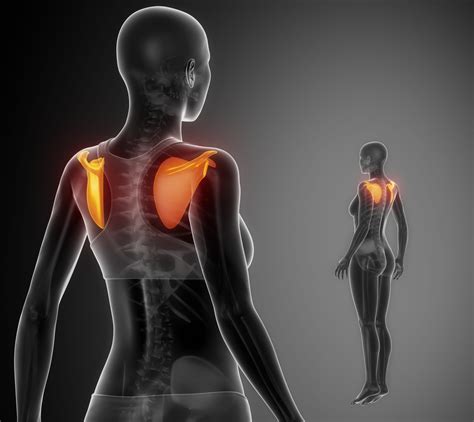

Understanding the Shoulder Blade

The shoulder blade, or scapula, is a flat, triangular bone located on the upper back. It plays a vital role in the movement and stability of the shoulder joint. The scapula connects to the humerus (upper arm bone) and the clavicle (collarbone), forming the shoulder girdle. This complex structure allows for a wide range of motion, making the shoulder one of the most mobile joints in the body.